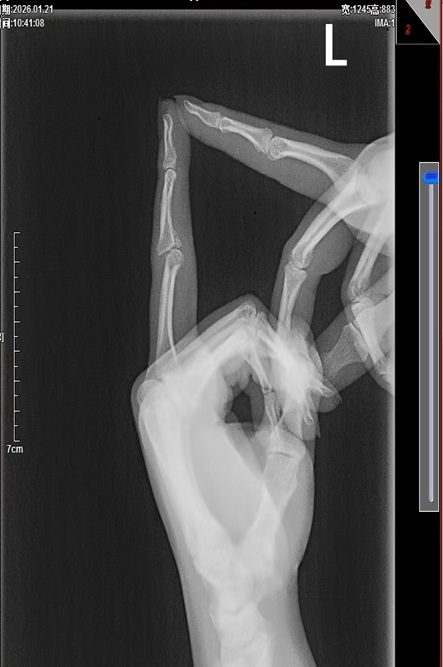

该患者因外伤导致环指PIP关节骨折,伤后自行使用手指夹板固定,保守治疗长达3个月,最终出现手指严重僵硬,关节活动受限,严重影响生活质量。曾于当地医院就诊,进行康复治疗后,活动度不仅没有好转,还发现近指间关节向背侧脱位,患者多方求医后来到我院就诊,手足及显微外科宋俊杰主任团队详细查体、评估影像学资料后,确诊为环指PIP关节陈旧性骨折脱位合并关节僵硬。